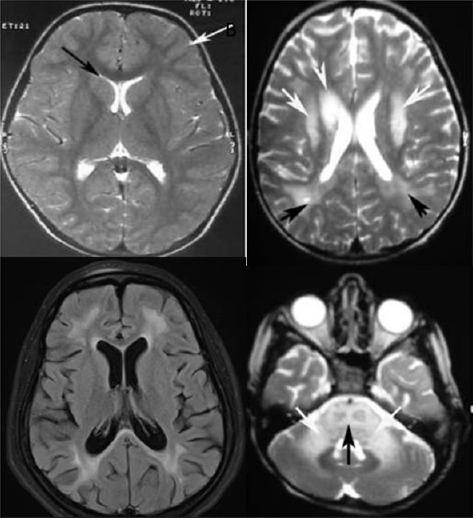

There were 33 patients with antimeasles antibody in CSF. Group 1 had 27 and Group 2 had 6 patients. Group 1 had lower age, cognitive dysfunction, slow myoclonus, less generalized tonic-clonic seizures, and focal seizures. Group 2 patients belonged to the higher age, had significant psychosis (P = 0.02), incontinence of bowel and bladder (P = 0.0001). Slow myoclonus was significant in the first group (P = 0.028), and weakness was significant in the second group (P = 0.028) and double incontinence in the second group (P = 0.0001). Magnetic resonance imaging showed significant gray matter and cerebellar involvement in Group 2 P = 0.005 and P = 0.028, respectively.

Patients who show significant titers of antimeasles antibodies in the CSF but belonging to older age group with psychosis, generalized tonic-clonic seizures, double incontinence, focal myoclonus, and electroencephalographic and imaging noncorroborative need to be investigated for autoimmune encephalitis in view of the great prognostic and therapeutic relevance.